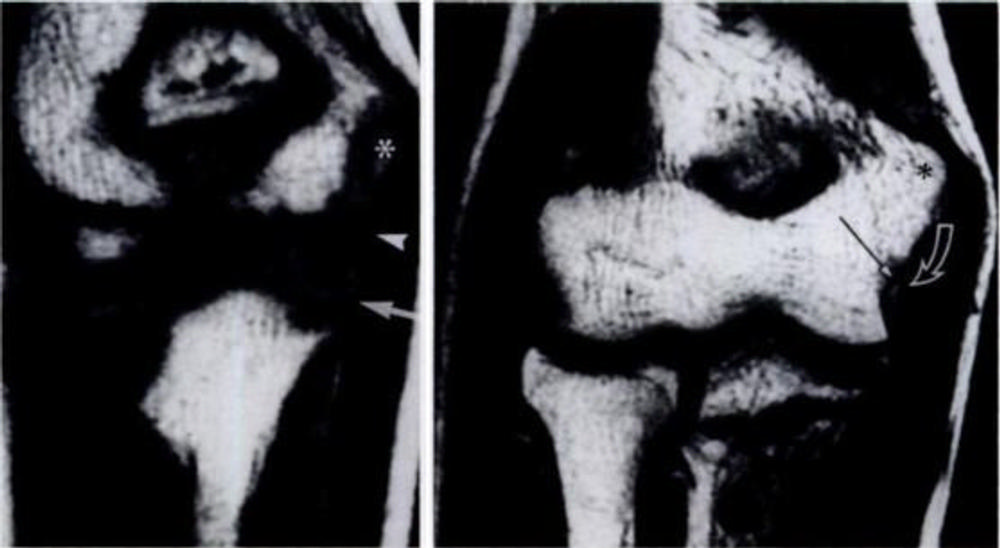

Figure 2. Elbow injury in 12-year-old boy. (Courtesy of Radiology)

Figure 4. MRI findings in elbow among pediatric baseball players and with respect to regional skeletal maturity.